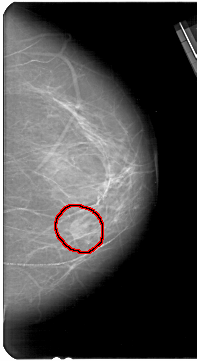

FILE: A_1681_1.RIGHT_MLO.OVERLAY

TOTAL_ABNORMALITIES 1

ABNORMALITY 1

LESION_TYPE MASS SHAPE ROUND MARGINS ILL_DEFINED

ASSESSMENT 4

SUBTLETY 3

PATHOLOGY BENIGN

TOTAL_OUTLINES 1

BOUNDARY